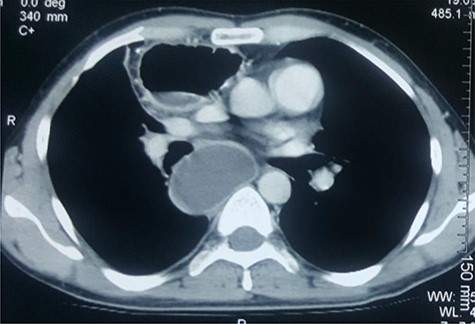

After unremarkable 18 months of the second surgery, he presented with a few days’ history of fever, dysphagia and a painful swelling in the left neck. There was an erythematous, hot cystic swelling measuring 6 cm × 5 cm in the neck underlying the earlier incision. Ultrasound of the neck revealed a loculated collection with some debris, without significant cervical lymphadenopathy. A contrast esophagram was performed which showed an intact esophagogastric continuity without obstruction, stricture, dilatation, leakage or delayed gastric emptying. A CECT scan revealed a distended blind-ended native esophagus filled with high-density fluid extending from neck to the diaphragmatic hiatus (Figs 1 and 2).

CECT of neck. Note the upper end of the pyocele displacing the trachea and the gastric conduit anteriorly and towards the right.

CECT of the chest. Note the huge pyocele posteriorly and the gastric conduit anteriorly.